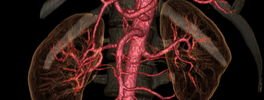

Kidney Angiography

Lower Limb Angiography